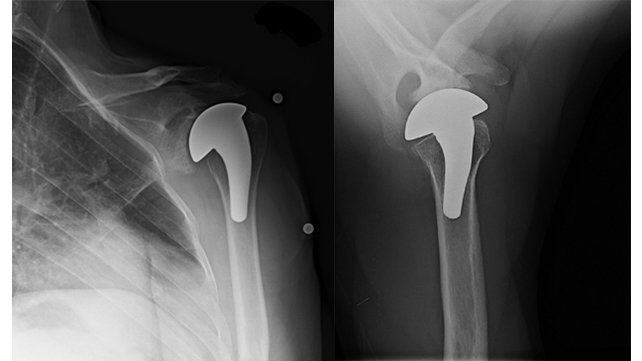

X-rays of a 43-year-old, active man with shoulder arthritis who was treated with humeral head resurfacing.

• Humeral head resurfacing removes the arthritic humeral surface and covers it with a metallic cap. This procedure preserves bone, allowing for possible revision surgery in the future.

• Stemmed humeral head replacements are much more commonly used and more extensively studied than humeral head resurfacing and stemless humeral head replacements.

(Fig. 5) X-rays of an active, 40-year-old man with shoulder arthritis who was treated with humeral head resurfacing.